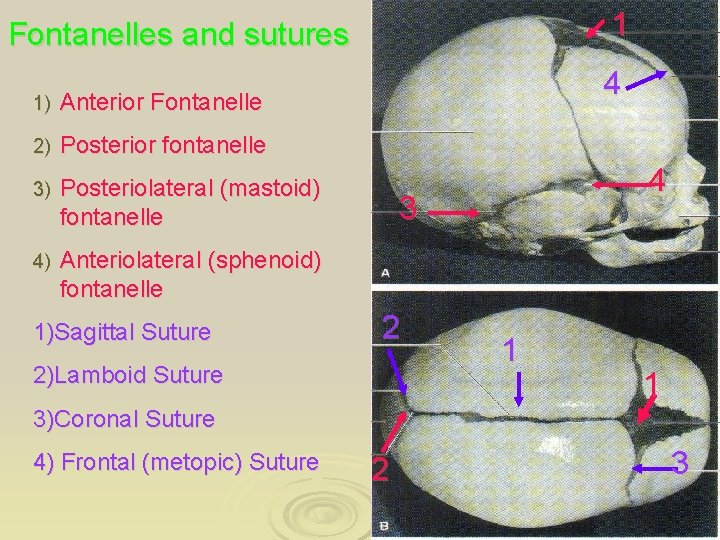

1 Fontanelles and sutures 1) Anterior Fontanelle 2) Posterior fontanelle 3) Posteriolateral (mastoid) fontanelle 4) Anteriolateral (sphenoid) fontanelle 1)Sagittal Suture 4 4 3 2 2)Lamboid Suture 1 1 3)Coronal Suture 4) Frontal (metopic) Suture 2 3